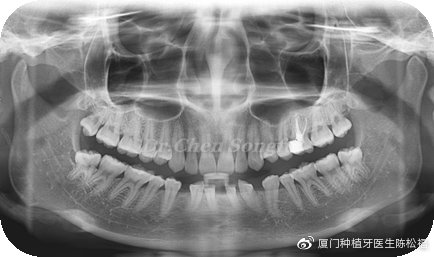

患者情况:E女士,24岁,下前牙先天缺失,存在散在间隙,覆合过深。

检查结果:下前牙从小存在间隙,影响美观。全口牙周情况良好,口腔卫生尚可。32,42缺失,41,31,43,33移位存多处散在间隙。咬合关系基本正常,前牙区深覆合

治疗方案:正畸种植联合治疗-联合治疗才是最佳方案

方案设计:行全口正畸治疗,31,41,33,43前移关闭前牙正中区间隙,预留33,43位置,改善前牙深覆合,33,43各种植一颗植体,完成最终修复。